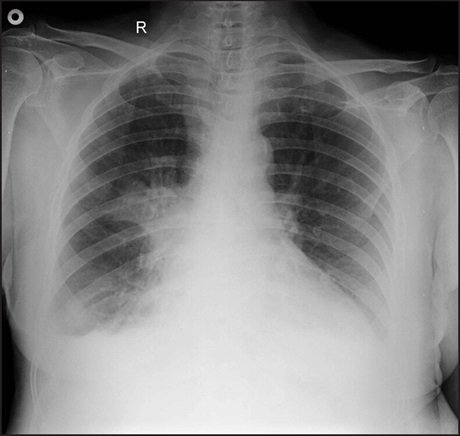

Young female patient with fever, cough and dyspnea.

Diagnosis? Image

Consolidation of the anterior segment of the RUL and the middle lobe of the right lung.

Moderate volume loss of the middle lobe. Image

Demonstration of Felson's silhouette sign.

On the PA view, the anterior segment consolidation is seen superior to the minor fissure of the right lung.